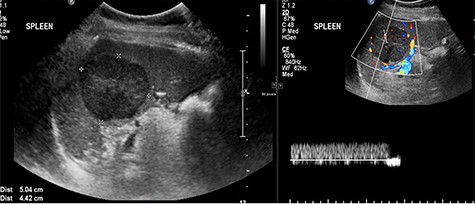

Abdominal ultrasonography showed a 5.0 × 5.0 cm well-defined, rounded, lobulated and hypoechoic vascular solid splenic lesion with no increased transmission or calcification. This lesion had vessels radiating from the center to the periphery (Fig. 1). Further evaluation with contrast-enhanced computed tomography (CT) of the abdomen showed a 6.0 × 5.6 × 4.4 cm solitary, rounded and lobulated non-calcified mass in the spleen, demonstrating heterogeneous, linear and nodular arterial enhancement with progressive filling in the portal venous and delayed phases (Fig. 2).

Ultrasound images with Doppler showing a well-defined rounded hypoechoic mass with vascularity in the peripheral areas as well as inside the lesion with no through transmission.